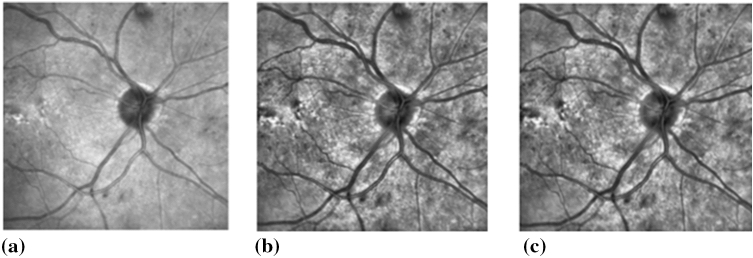

A median filter is a nonlinear filter with edge-preserving properties that reduce noise without compromising the edges. This was used to remove the Gaussian and Speckle noise68. Contrast enhancement was performed by using CLAHE with regional operations and suitable retinal images, which may have light intensity variations across the image69. Figure 3 shows an example of the pre-processing performed on IR retinal images prior to feature extraction.

Figure 3.

An example of pre-processing operations performed on the IR retinal image. (a) Original IR image. (b) IR image after performing CLAHE. (c) Median filtered IR image.